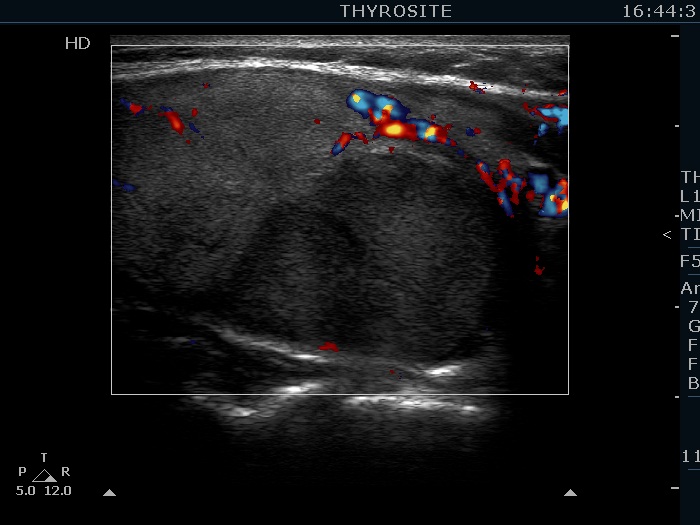

The echogenicity of the nodule - case 2158

Examination 3 years later (ultrasonographic picture 7)

Right lobe, another longitudinal scan, color Doppler mode. The nodule shows sign of perinodular blood flow.